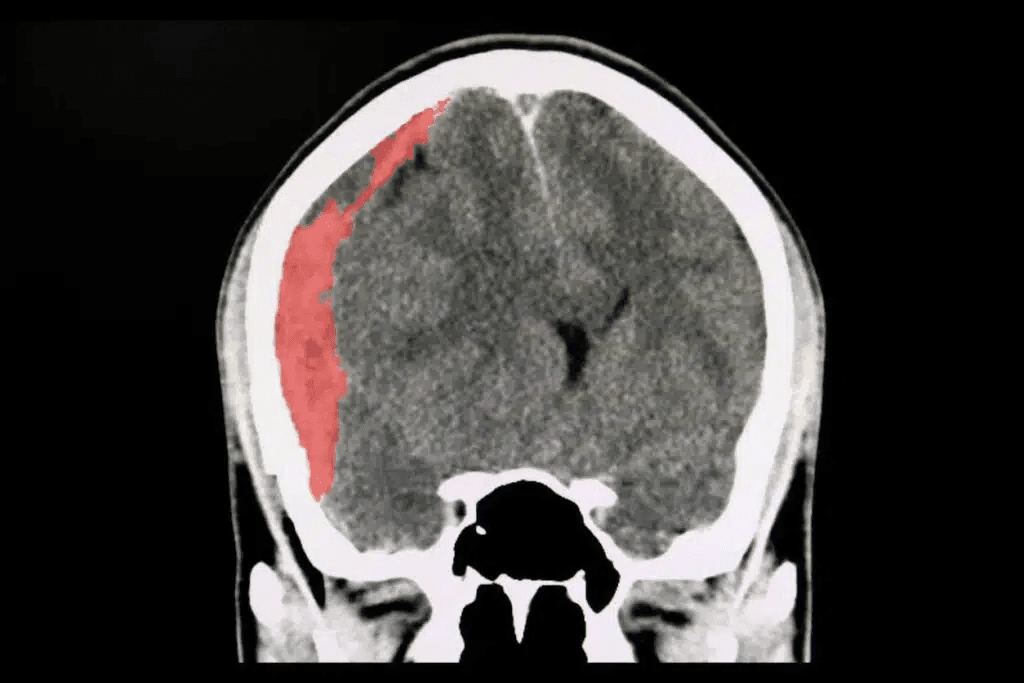

A CT scan of the brain of a patient with trafic accident showing acute subdural hematoma.

A subdural hematoma is a collection of blood outside the brain. Subdural hematomas are commonly caused by a blow to the head when a blood vessel bursts between the lining of the brain and the brain itself. As a result, a collection of blood pools between the brain and the lining of the brain.